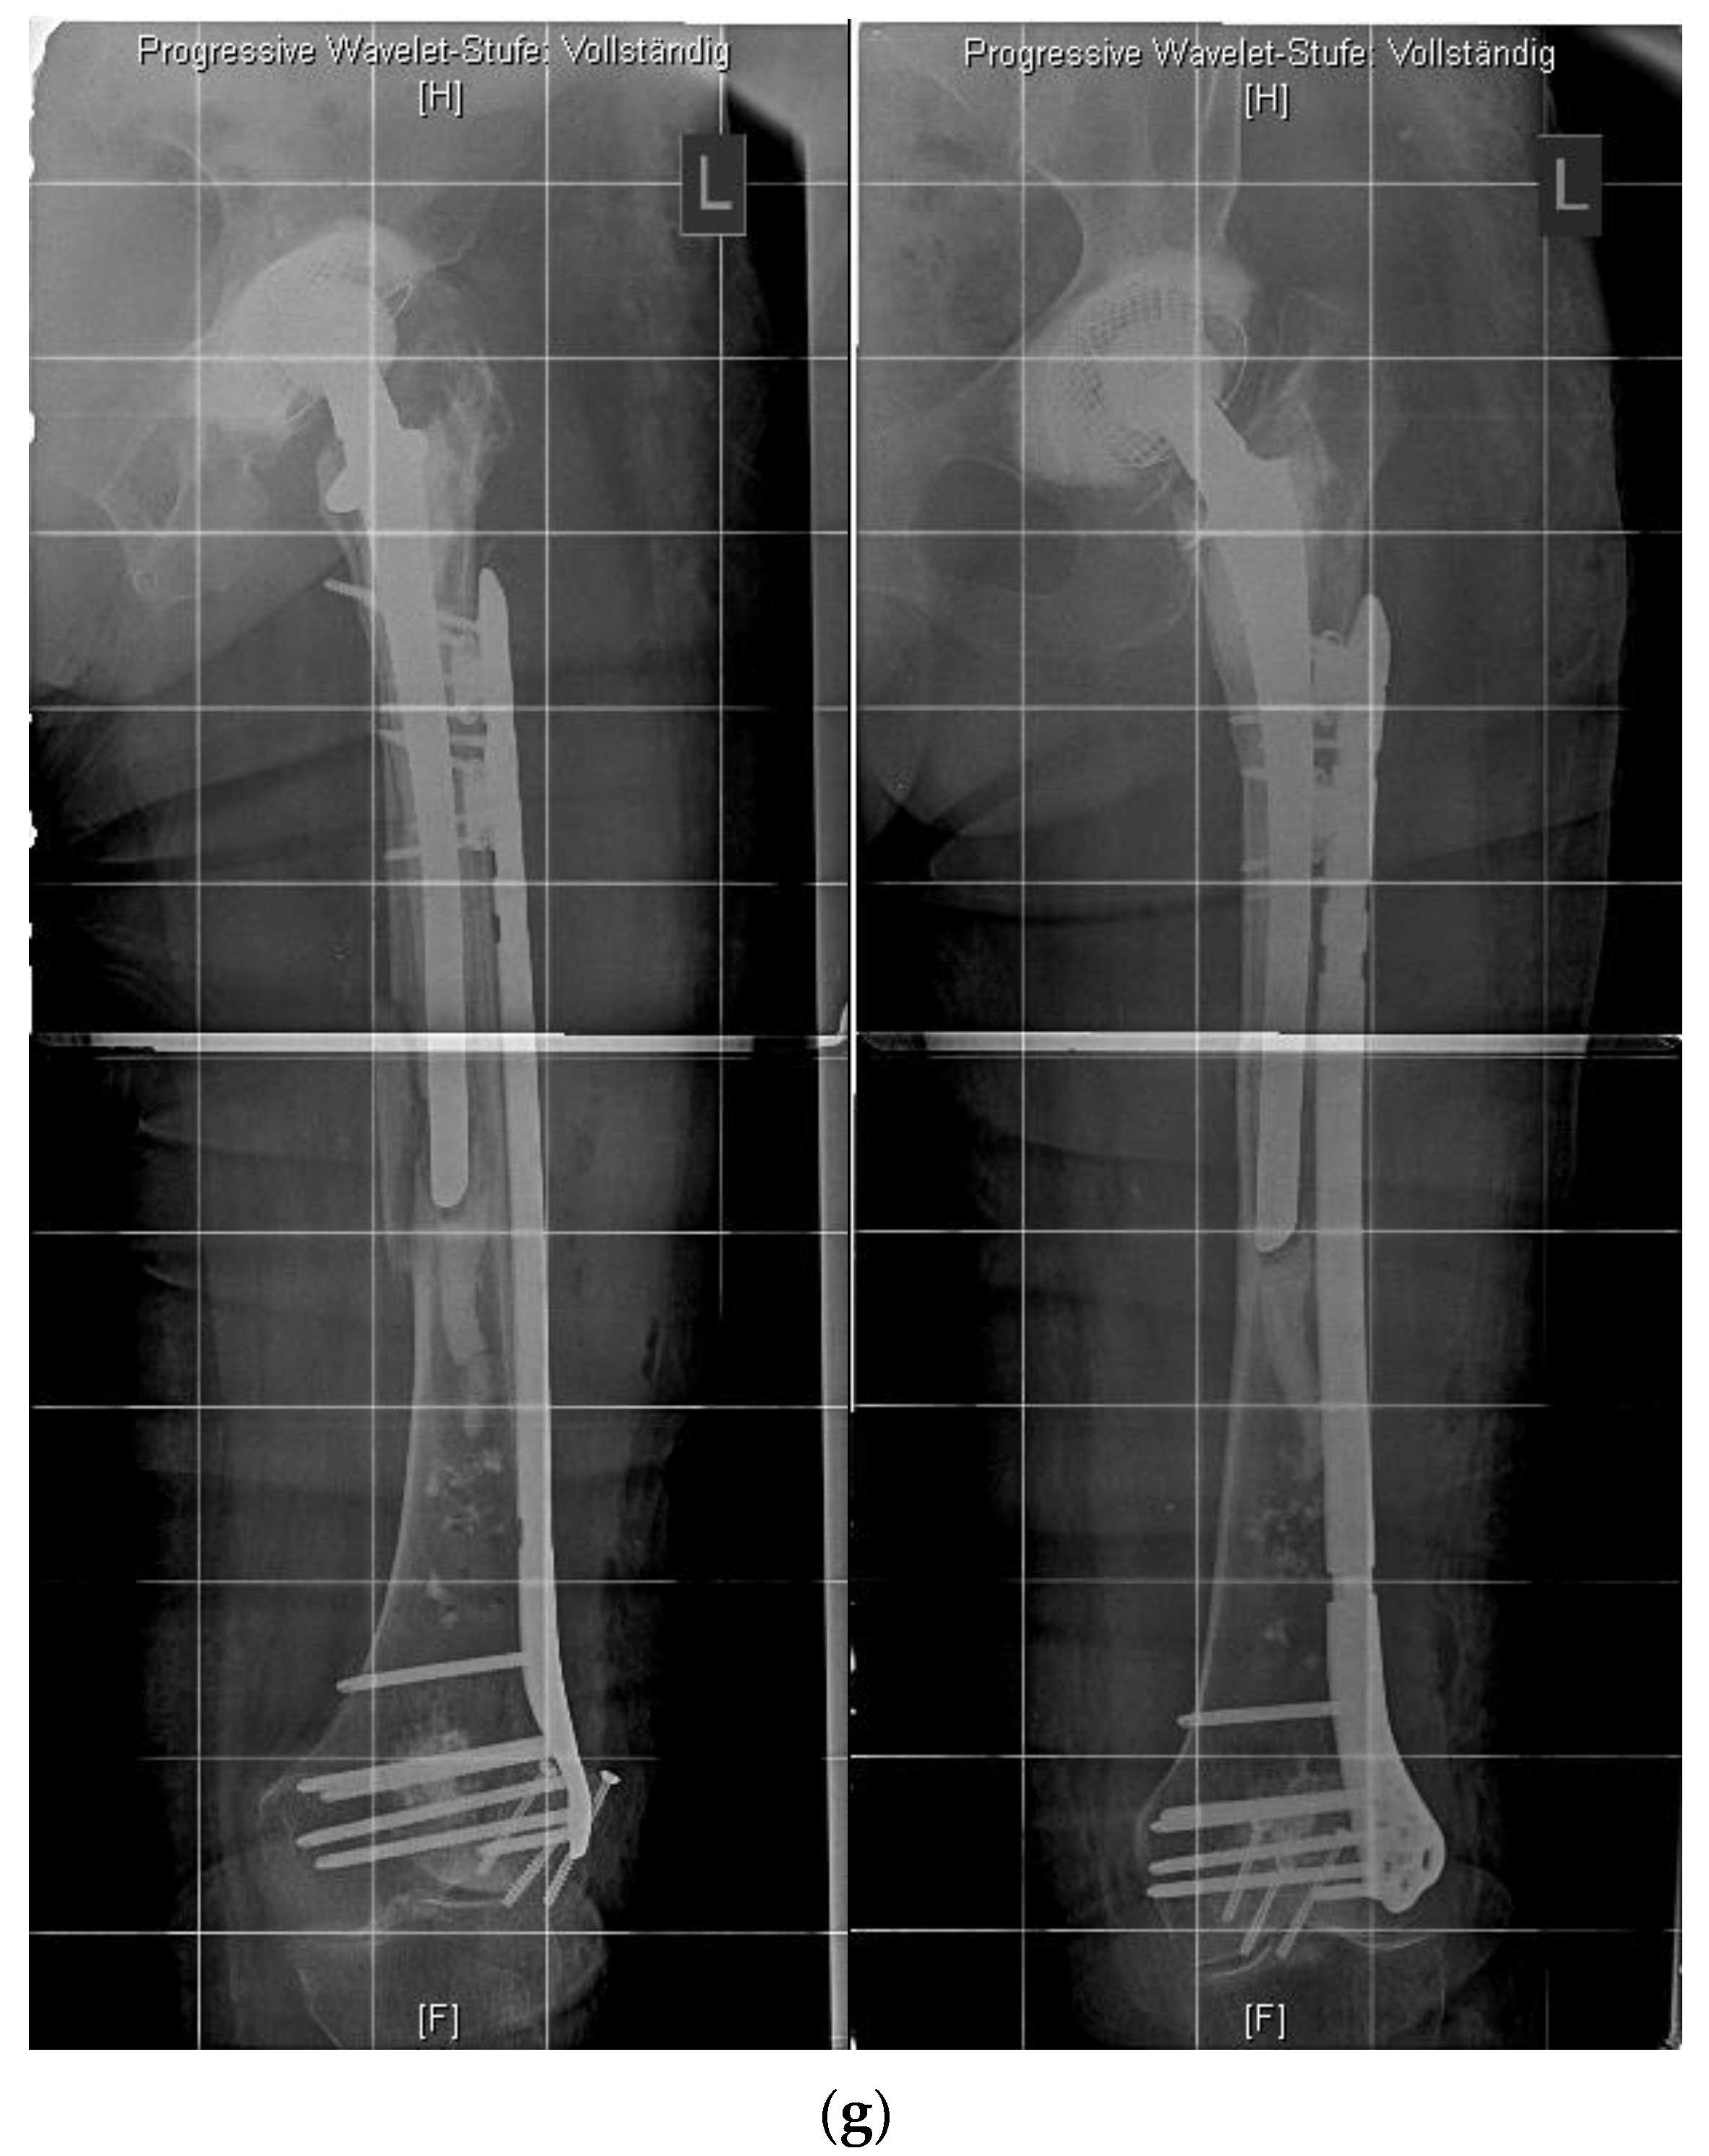

Although rare, interprosthetic fractures require cautious preoperative planning. Depending on the quality of the bone stock and the implant stability, either osteosynthesis via locked plates, the use of special devices such as docking tools (“Osteobridge®”, Merete Medical, Berlin, Germany) or custom-made interposition sleeves (AQ-Implants GmbH, Ahrensburg, Germany; “RescueSleeve®”, Waldemar Link GmbH, Hamburg, Germany) should be considered to avoid revision total hip replacement (RTHR) or a total femur implantation.

The “Osteobridge®” is a modular system which spans the fracture according to the distal and proximal end, respectively, over the implant stems of the endoprosthesis [29]. Interposition devices, such as the “RescueSleeve®”, are used to replace the fractured diaphyseal bone and to couple both ends of the hip and knee stem using two screws connecting the sleeves (Figure 5) [30], while custom-made sleeves could be used to couple a stable implant to a tumor endoprosthesis (AQ-Implants GmbH, Ahrensburg, Germany) (Figure 6).

Figure 5.

Custom-made interposition sleeve (Waldemar Link GmbH, Hamburg, Germany).

Figure 6.

Interprosthetic fracture around a stable total knee revision arthroplasty and a loose total hip revision arthroplasty. Implantation of a custom-made docking sleeve coupled to a proximal femur replacement (AQ-Implants GmbH, Ahrensburg, Germany).